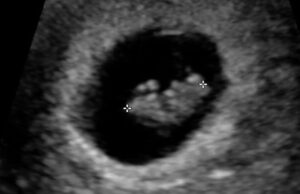

The chemical abortion pill is now more accessible than ever, available online, in pharmacies, and even by mail. It’s marketed as quick, easy, and private. But behind that convenience is a baby fighting for life and a woman in crisis, scared and searching for hope. Women are now being reached earlier, often before they’ve had a chance to see an ultrasound or talk to someone who will truly listen. Many are overwhelmed and convinced that abortion is their only option.